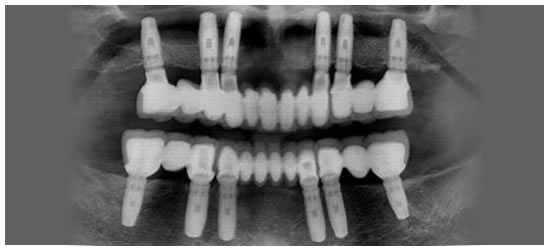

See photos of a complete dental implant case